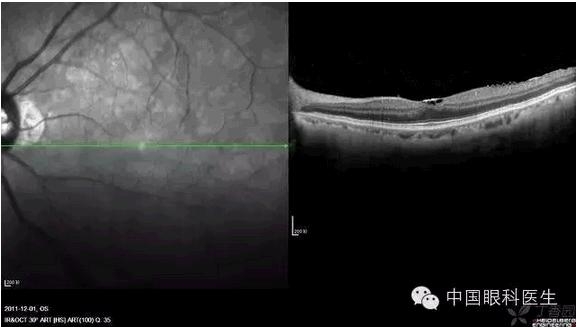

视网膜色素变性:除黄斑区仅余的IS/OS反射光带外,余未见IS/OS反射光带。